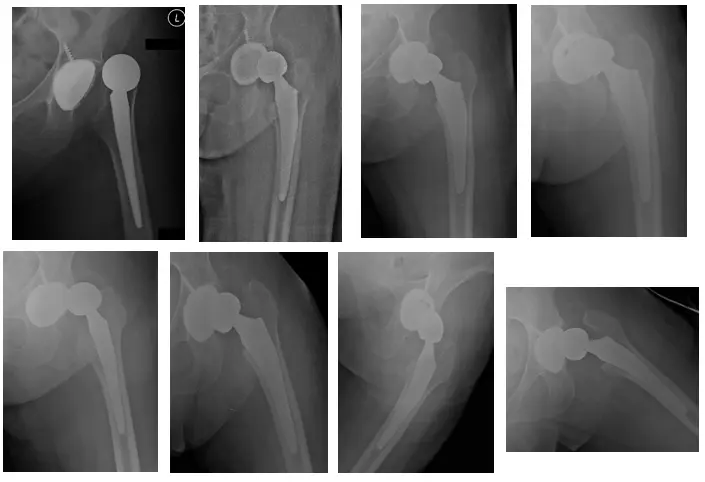

Radiografías postoperatorias de caderas bilaterales

Las radiografías muestran una THA izquierda con un liner constreñido